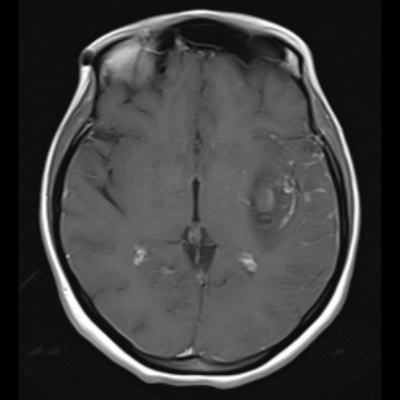

- Kontrastlı T1A görüntüde (C) ve kontrastlı T1A çıkarma görüntüde (D) medialde bulunan alanda kontrastlanma izlenmezken (ok), lateralde bulunan boyutça daha küçük alanda kontrastlanma izleniyor (ok). Ayrıca anevrizma komşuğunda silvian fissürde leptomeningeal kontrastlanma görülüyor.

- Kontrastsız BT görüntülemede (E) bu düzeyde intraparankimal kanama ile uyumlu hiperdens alan gözleniyor (ok).